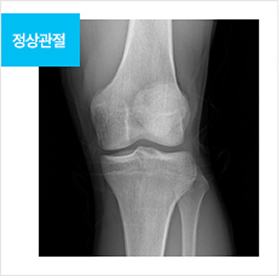

수술 전후 무릎관절 변화

뼈가 맞닿아 통증을 유발하던 공간이 확보되어 통증이 완화되며, 본래의 관절 운동 기능이 회복됨

정상관절 img before img after img